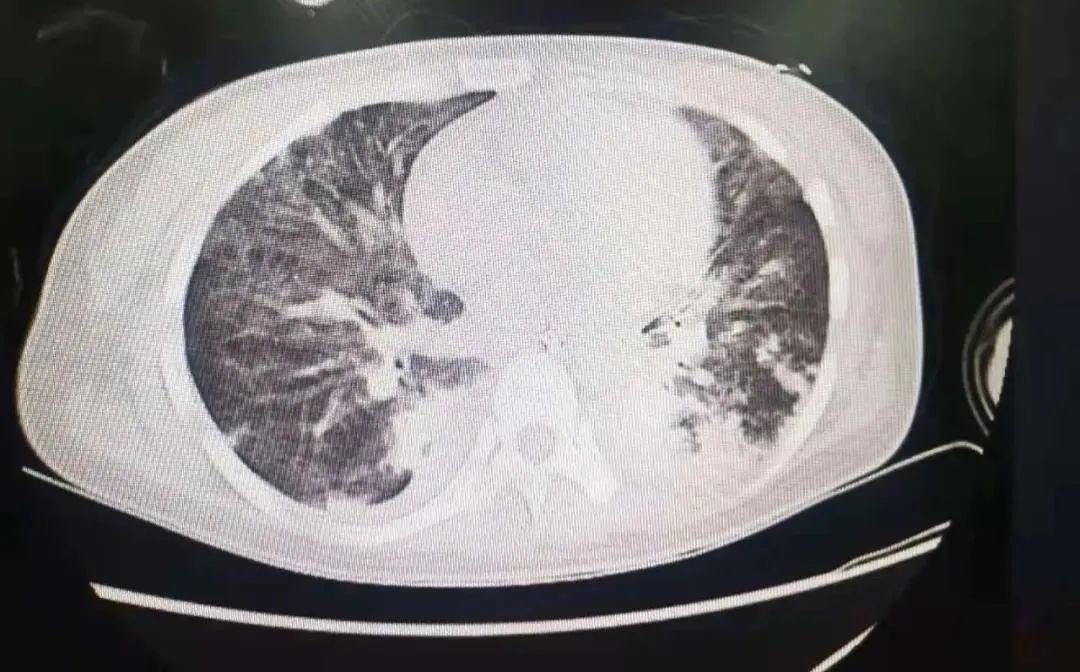

莹莹严重的“白肺”

“根据检查结果和指标,看起来确实像严重的感染性肺炎,但多次病原学检查都没有发现感染源,这与常见的肺炎又不一样。”重症医学科副主任、之江院区监护室主任李彤副主任医师说,他们为莹莹再次进行了肺部CT检查。

在梳理检查指标时,一个数值引起了专家团队的注意:莹莹的血钙指标大大超过正常水平!结合莹莹的肺部CT的影像图,ICU专家团队发现了蛛丝马迹!

“莹莹肺部的CT影像变化,很像一种临床上非常罕见的疾病表现!”进一步对比国内外文献报道,果然,在甲状旁腺功能亢进病例中,他们找到了这种个例,而这种情况在全世界的文献中只报道过几例。

【 女子|30岁女子两肺“发白”被疑严重肺炎?没想到竟是肺里堆满了它】原来,莹莹肺部的白色阴影并非感染,而是大量沉积的钙离子。莹莹因甲状旁腺腺瘤引发了甲状旁腺分泌过多甲状旁腺激素,导致甲状旁腺功能亢进。甲状旁腺激素的主要功能就是调节人体内钙、磷的代谢,而甲旁亢患者因为激素异常变多,会使骨头里的钙大量进入血液,导致钙离子在一些组织中异常沉积,使组织发生病理性钙化。而这种钙离子异常沉积发生在肺里的,目前国际上可查阅文献中也只有极少数的个例。